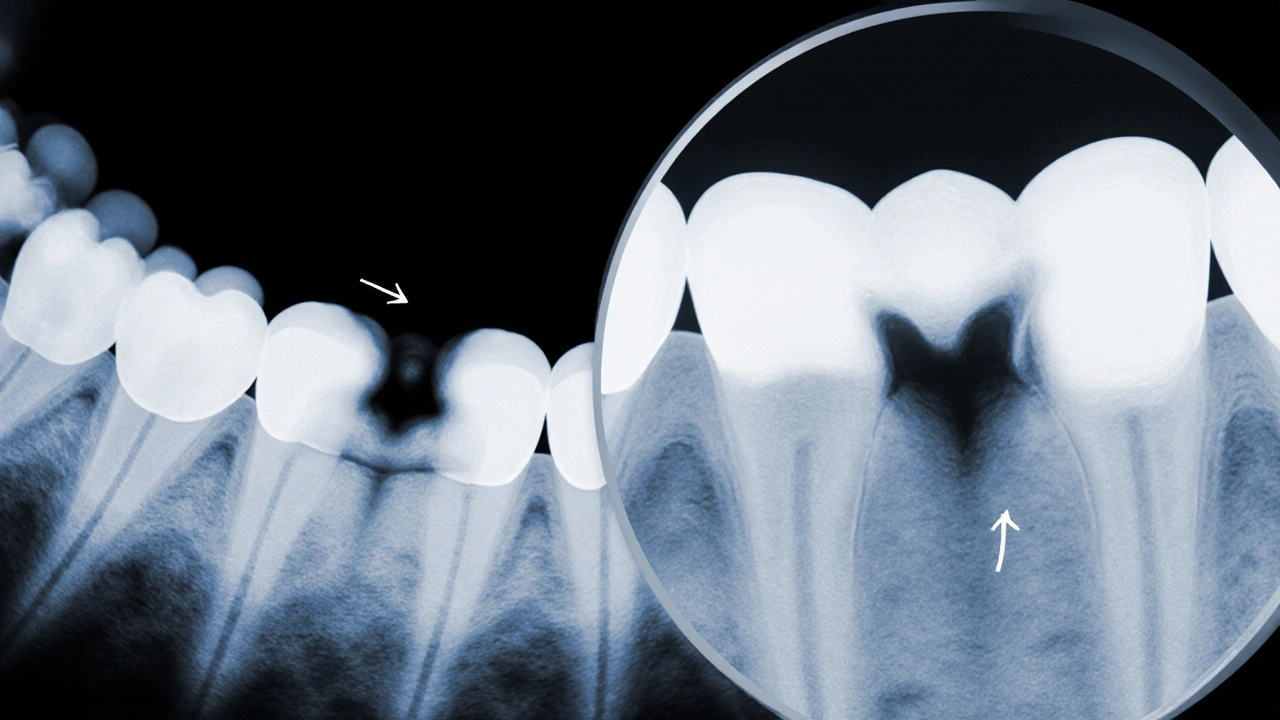

Vizualizace a sonda jsou jen začátek. Pro potvrzení kazů mezi zuby je třeba rentgen. Nejčastěji se používá bitewing rentgen - malý film nebo digitální senzor, který se vloží do úst. Ten zachytí zuby od korunky až po kořen a ukáže, jak vypadá mezera mezi nimi zevnitř.

Na rentgenovém snímku se kaz objeví jako tmavší oblast ve světlé sklovině. Čím tmavší, tím větší je poškození. Zubař může vidět, zda je kaz jen na povrchu, nebo už pronikl do dřeně. Tímto způsobem ví, zda stačí malá plomba, nebo jestli je třeba více práce.

Digitální rentgeny dnes používají 80 % méně záření než staré filmové. A snímky se zobrazí hned - zubař vám je může ukázat na obrazovce a vysvětlit, kde je problém.

Rentgenový snímek ukazuje kaz mezi zuby jako tmavou oblast ve sklovině.